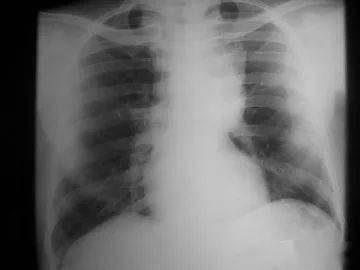

胸腺癌的治療,要根據(jù)TNM的分期來選擇。術(shù)后治療的選擇,要有明確的病理證實是R0、R1或R2手術(shù),如果是R1手術(shù),美國NCCN指南(2012 Version2)推薦術(shù)后放療+化療,R2手術(shù)也如此。關(guān)于是否照射心包,要根據(jù)術(shù)前的CT,看是否有心包受累來決定。心包的耐受量,三維適形放療(DT45-50GY)應該沒有問題,如果長期生存的年輕者,全心臟的受量要限制在30GY以內(nèi),另外要選擇非蒽環(huán)類的藥物。放療后要補2-3個療程的化療。